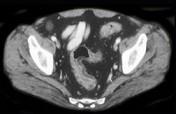

问题 男,35岁,腹痛、腹泻、腹胀、脓血便、里急后重,结合图像,选择最可能诊断 ( )

选项 A.溃疡性结肠炎 B.结肠克罗恩病 C.结肠结核 D.假膜性肠炎 E.结肠淋巴瘤

答案 A